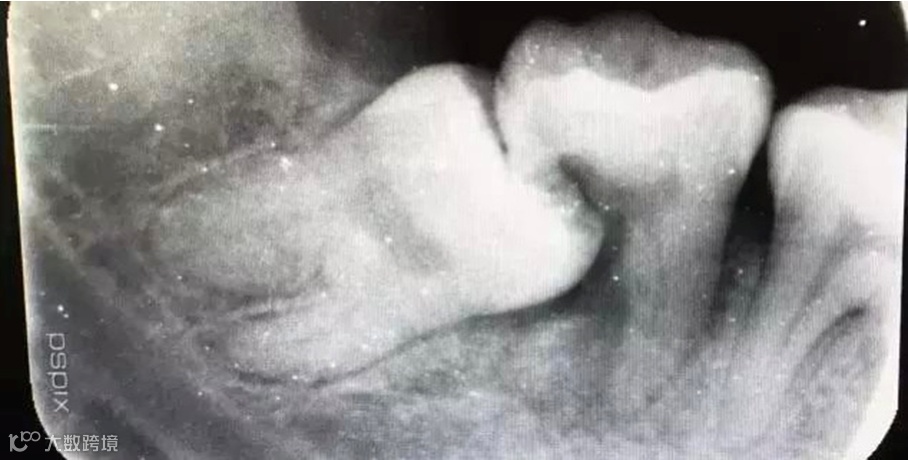

3、阻生的智齿往往不能与对颌牙齿建立正常的咬合关系,长时间可导致颞下颌关节弹响、张口疼痛,夜磨牙等症状,如果在上颌的智齿,往往向颊向阻生。咬合的时候,会咬到颊黏膜,引起颊黏膜的损伤、溃疡,对轻壮年的身心健康影响较大。

如果智齿完全埋伏在颌骨当中,它还在不断萌出,就可以压迫第二磨牙远中的牙根,引起牙根吸收。